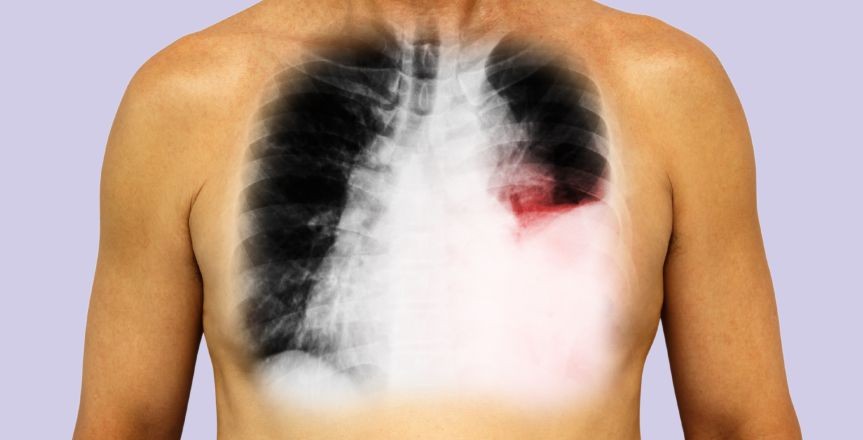

Pleural Effusion

The accumulation of fluid in layers in the layer between the lungs and chest cavity. A small amount of fluid is present in this cavity for lubrication during breathing, but too much accumulation can cause a problem, which is stated as pleural effusion.